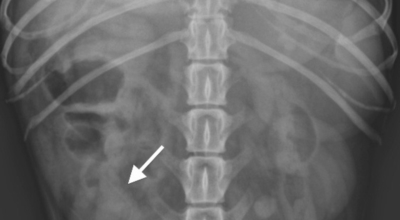

일반인이 근육통과 금이 간 경우의 차이는 거의 판별하기 힘들어요. 갈비뼈라고 하는 부분이 눈에 보이도록 붓는 것도 아니고, 멍이 들어서 아픈것도 아니기 때문이지요. 가장 정확하게 판별하는 방법은 엑스레이를 찍는 방법이지요.